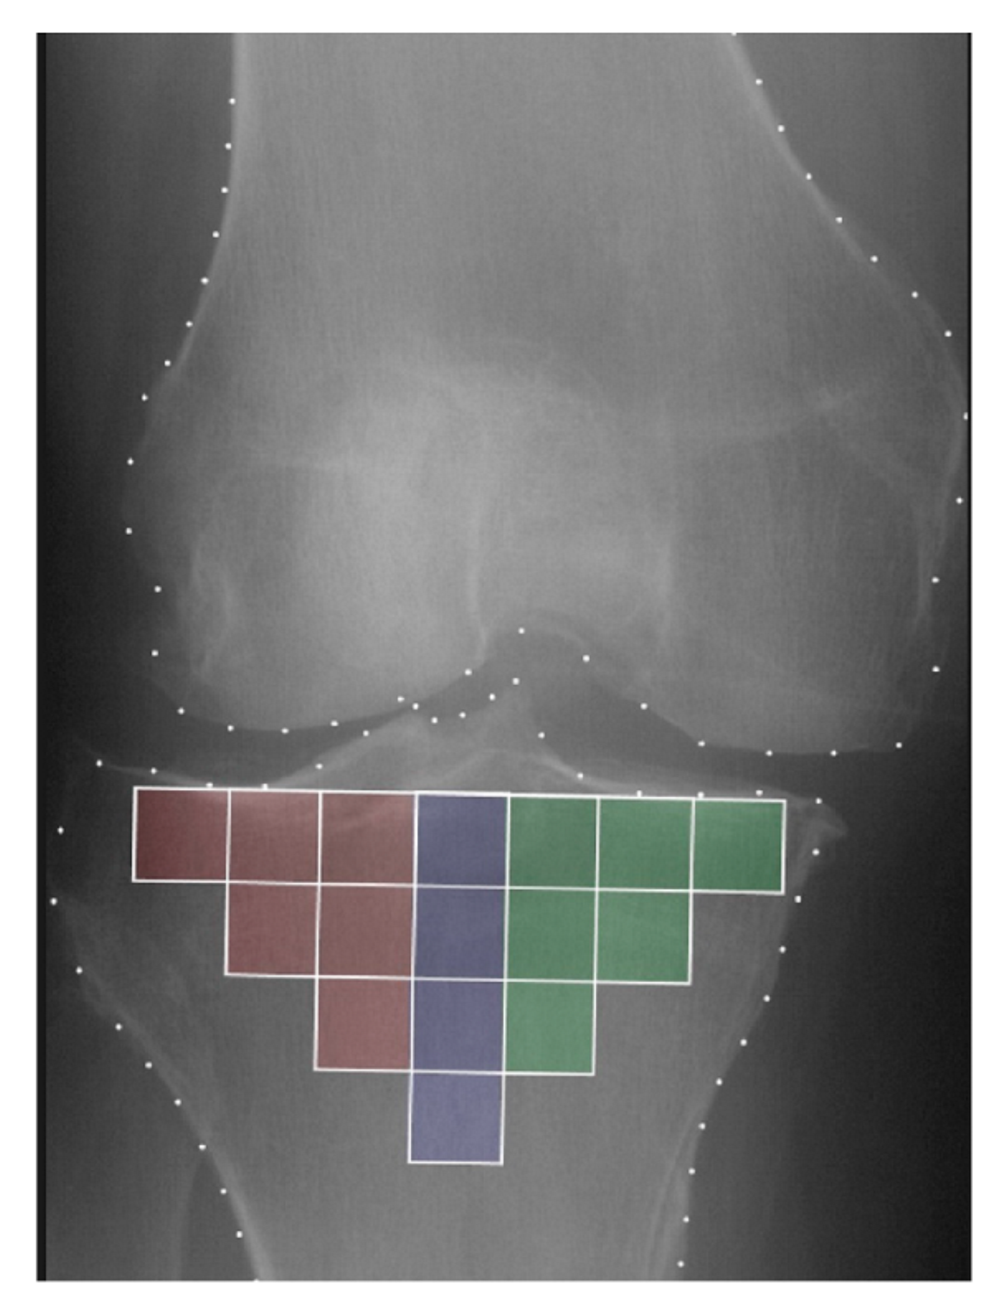

2.3. Trabecular Bone Texture Analysis